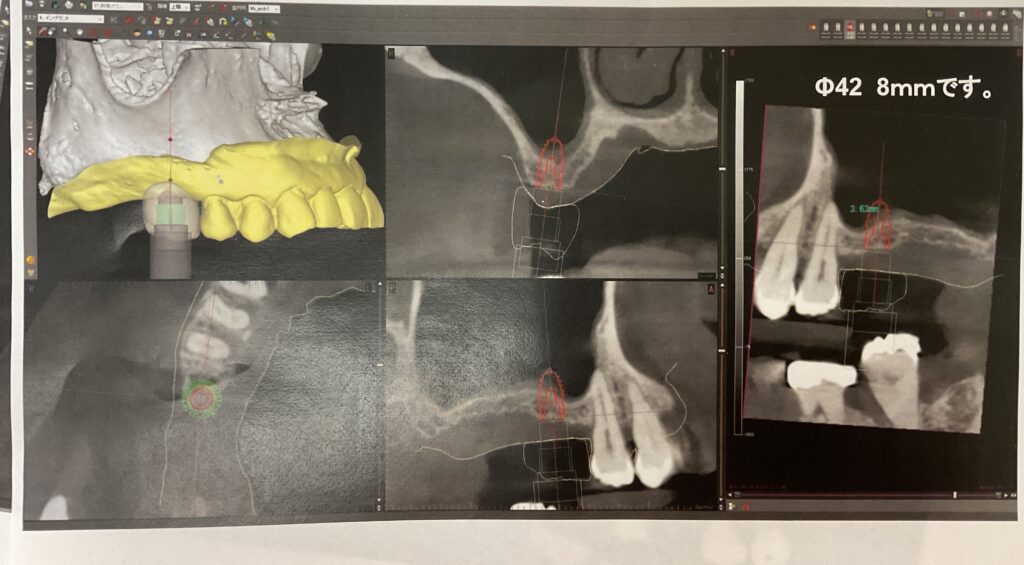

CT撮影の重要性

骨の高さ・幅・厚み、神経・血管などを3Dで把握することで安全な位置・角度で計画することができます。

サージカルガイド作製の重要性

サージカルガイドシステムのインプラント治療とは、予めCT撮影なのでシュミレーションを行い設計されたガイドのマウスピースをはめて手術を行う技法です。

設計通りに正確な位置でインプラントを埋入でき、手術は低侵襲で術後の痛みも出にくいのがメリットですが一方、マウスピースを作製するコストがかかることや、技術を持った歯科医師が限られている事がデメリットにあげられます。

骨の深さや方向など、正確な位置にインプラント体を埋入するガイドを作製する為の資料としてCT撮影と口腔内の模型を取ります。

クリニックで撮影したCT画像を元に歯科医師と歯科技工士がどの位置にインプラントを埋入するか話し合い、歯科技工士がサージカルガイドを作製します。